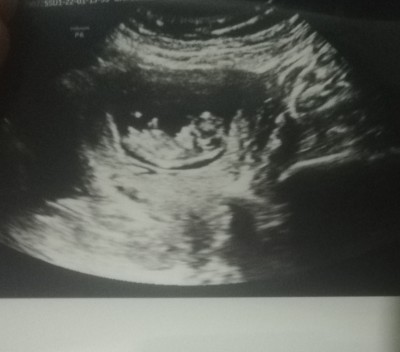

Kafasi poposu nerde bu cocugun?

Bunda daha tam 17 haftalık değildi ben çoktandır gitmemişim doktora bu en son çektiğim ultraston

Erkek bence doktorun tahmini ne.

Ben de bilmiyorum cnm en son gittiğimde belli birşey yoktu

Kızda olabilir